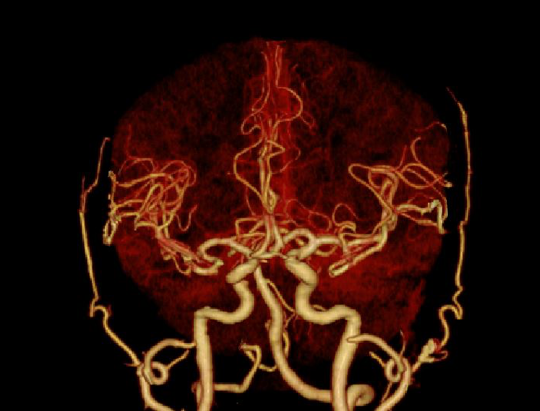

基于AI技术,对搏动的冠脉进行精准的识别、追踪、运动建模和运动伪影校正

3D打印精密工艺三维防散射栅格、Real 3D Full大锥角重建算法等多重硬件、软件技术协同,克服宽体探测器的核心技术挑战,天河640单圈扫描即可获得高质量的全脑、全冠脉轴扫图像